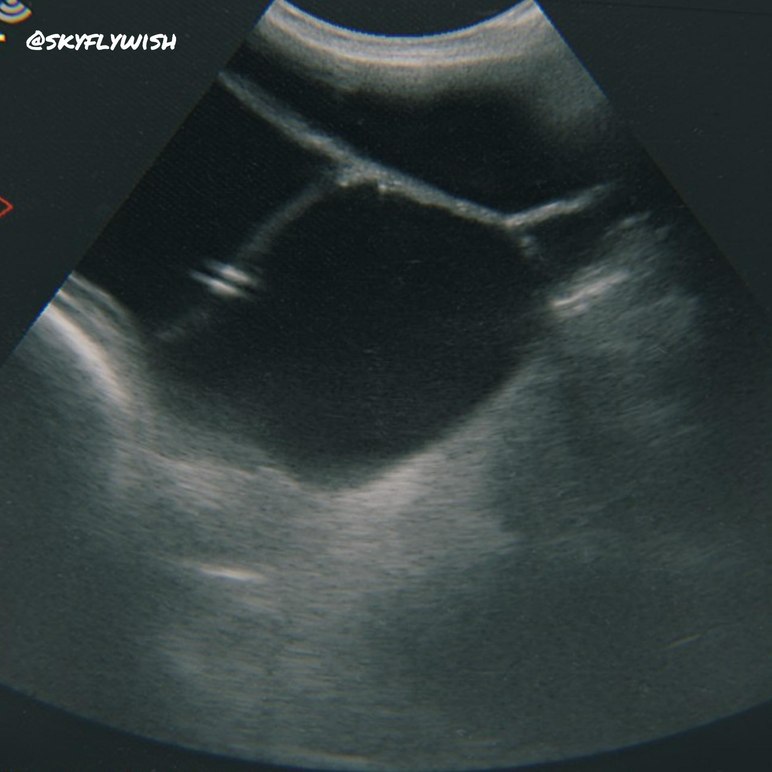

Ложная беременность или гидрометрия (falsum gravida)-довольно распрастроненная дисгормональная патология и причина бесплодия у коз. Это заболевание характеризуется длительной анафродиаией, персистенцией одного или нескольких функционально активных жёлтых тел в яичниках и объёмным увеличением размеров матки за счёт транссудации (выпота) в её полость стерильной серозной жидкости.

Поэтому очень важна плановая УЗД.

От животных, переболевших гидрометрией, получается потомство, которое имеет гарзадо бОльшие риски заболеваемости этой патологией, чем здоровые особи. (примерные риски 35-40% от больных и примерно 9% от здоровых). Данную патологию в 100% можно выявить только УЗИ. Особого лечения патология не требует. Важна профилактика авитаминоза - витаминные комплексы( например, мультивит минералы(Se)). А так же прерывание прогрессирующего процесса - гормональные препараты.

Всё УЗ снимки были сделаны Емельяновой Дарьей на хозяйстве в Белгородской области.